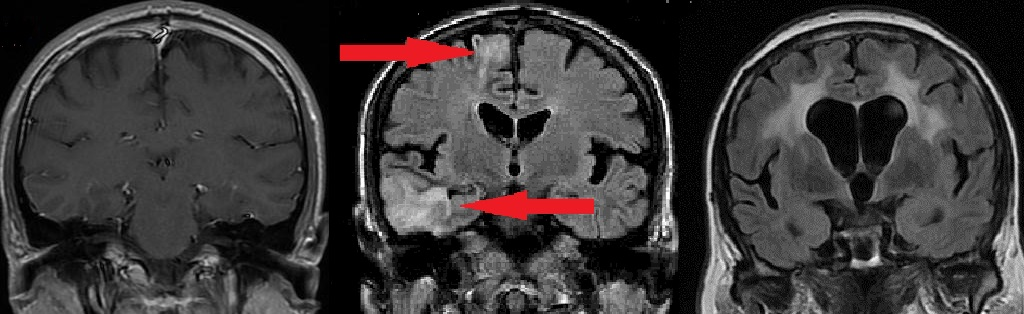

МР-томография головного мозга. Мозг выглядит серым, цереброспинальная жидкость – черной, пострадавшие участки мозга – белыми.

- СЛЕВА – нормальный мозг.

- В ЦЕНТРЕ – мозг частично замещен на жидкость, стрелками обозначены очаги сниженного кровообращения. Причина – образование тромбов из-за нарушений ритма сердца + попадание этих тромбов в мозг.

- СПРАВА – масса мозга всерьез уменьшена с замещением на жидкость, белые пятна – область массовой гибели клеток мозга. Причина – сужение сонных артерий на 75% и 80% холестериновыми бляшками.